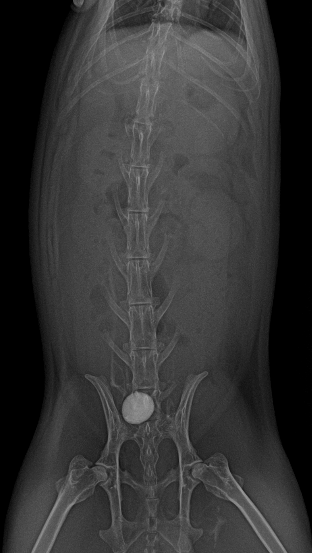

超音波検査では膀胱内に結石がみられました。レントゲン検査にて個数と、他の場所にも結石がないかどうか確認をしました。